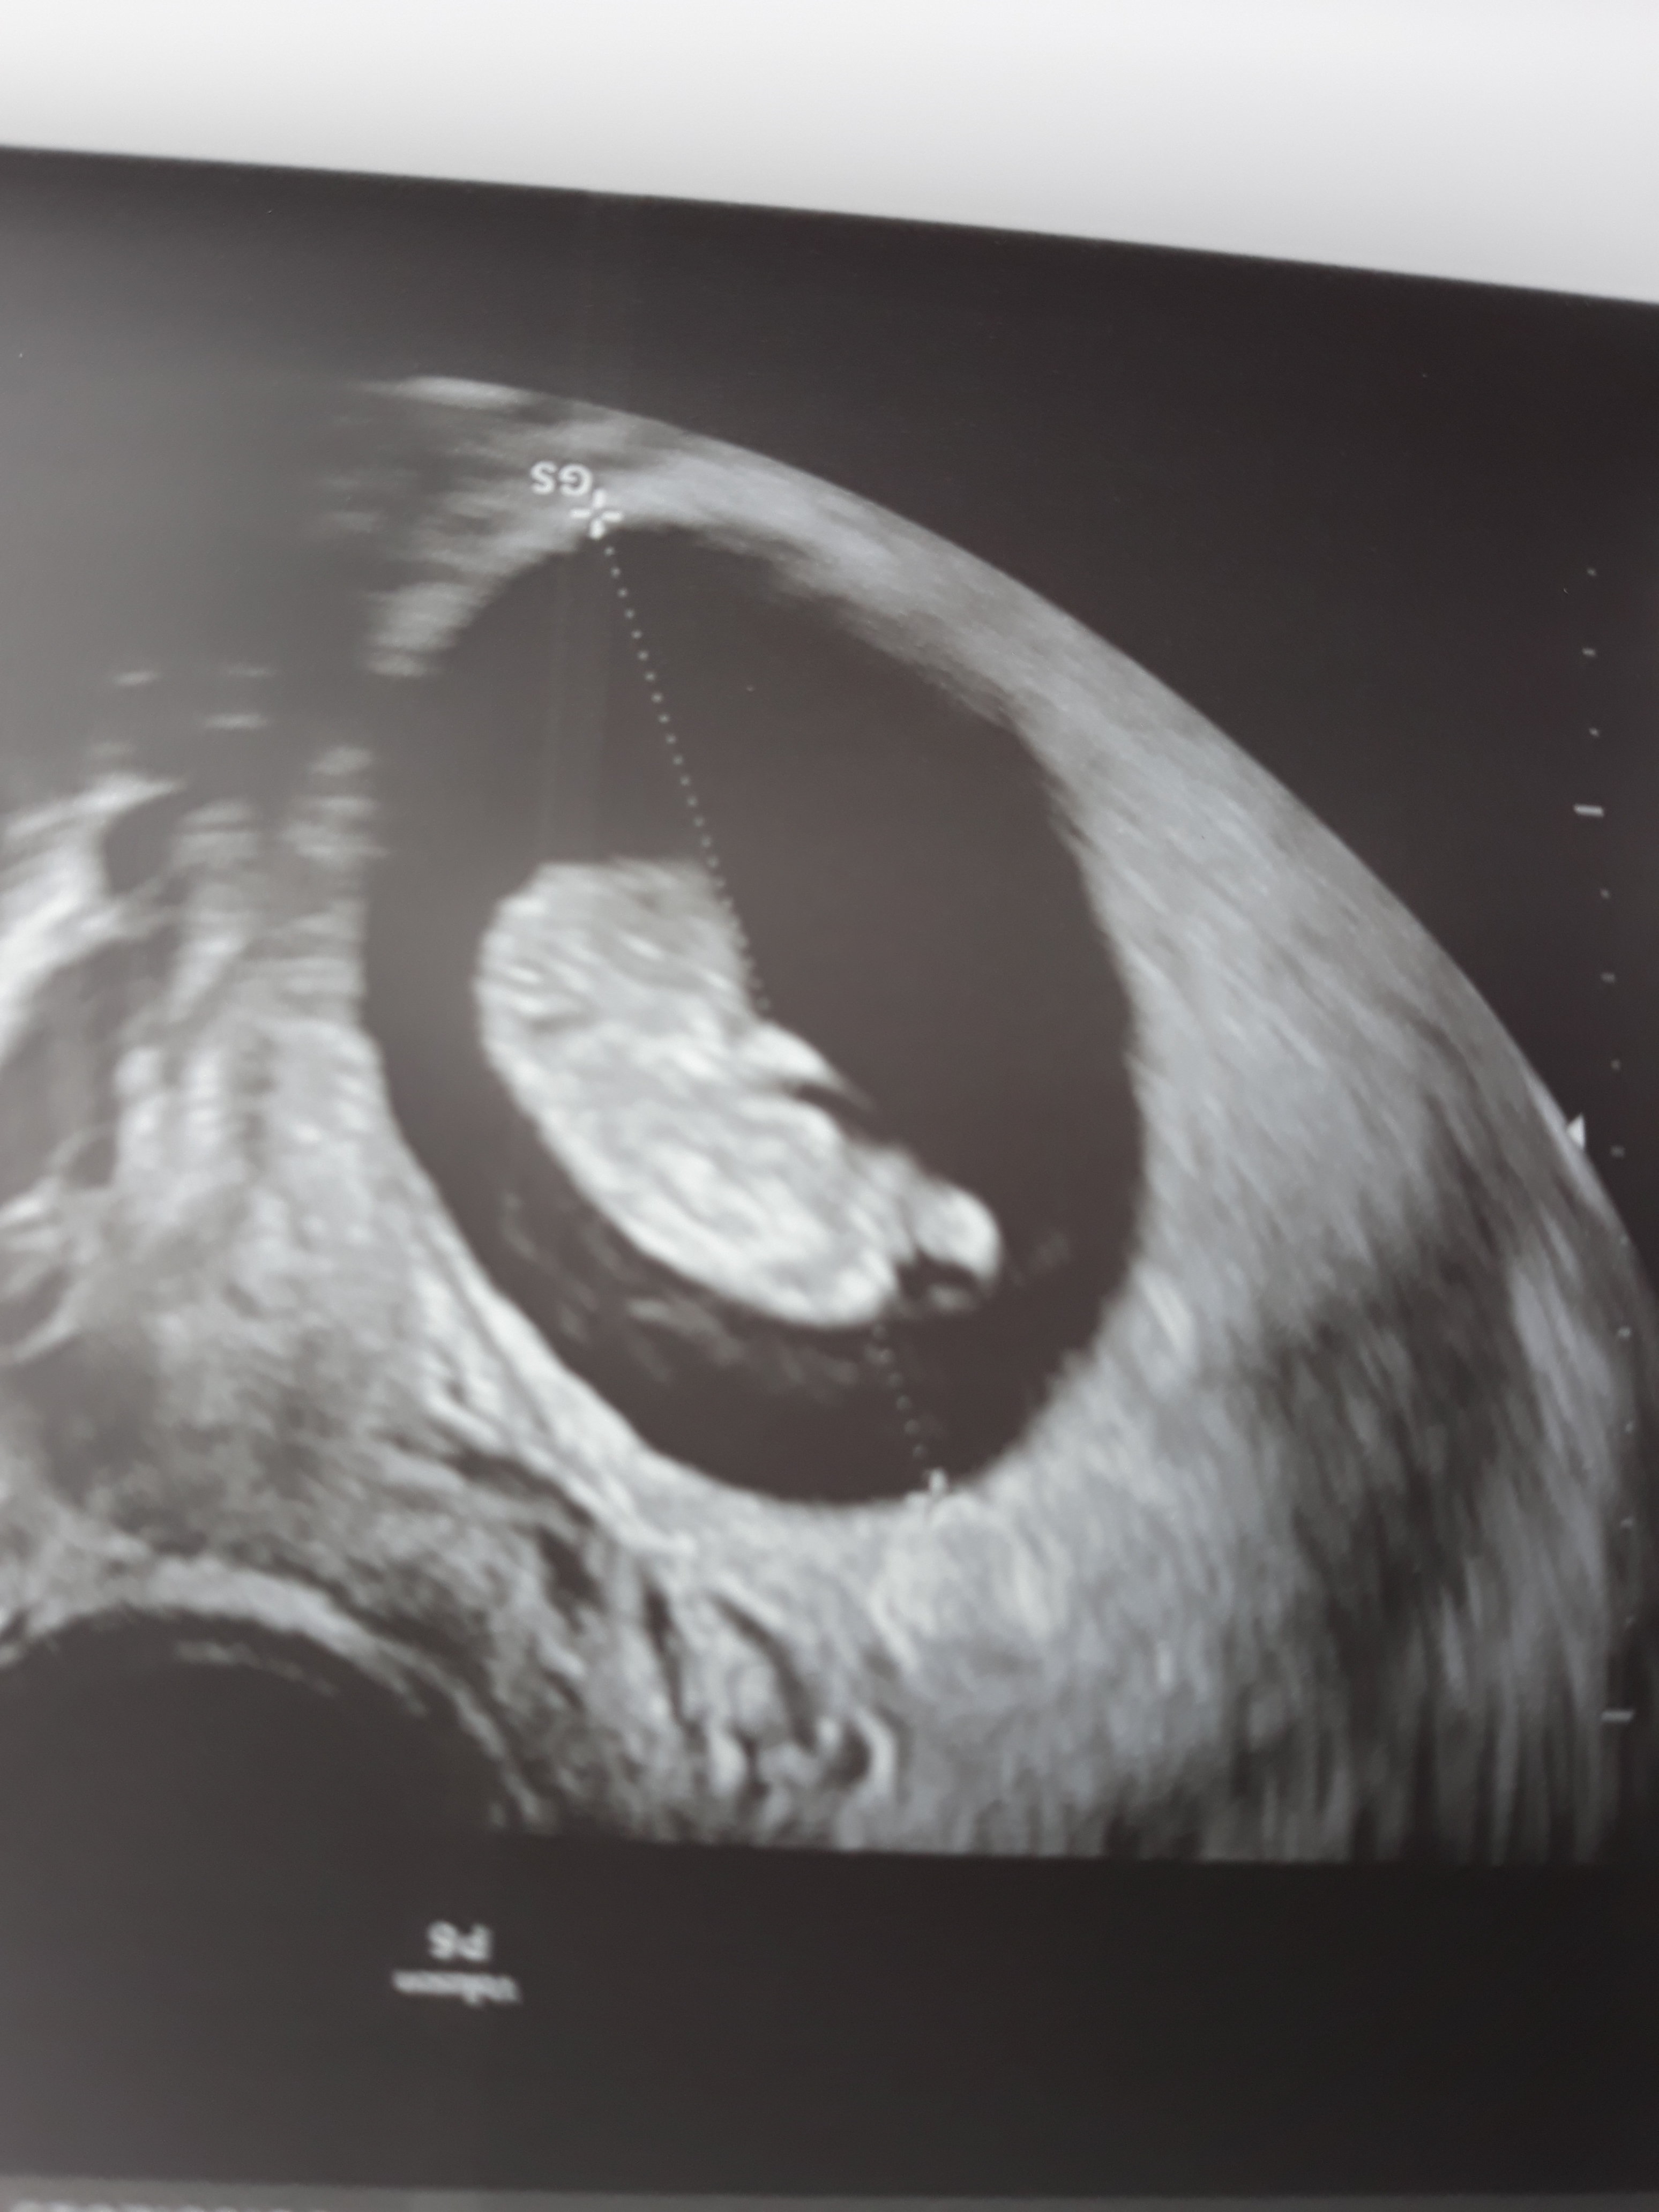

Ja już po wizycie dzidzia ma się dobrze 2.5 cm serducho bije

20190508_134025.jpg